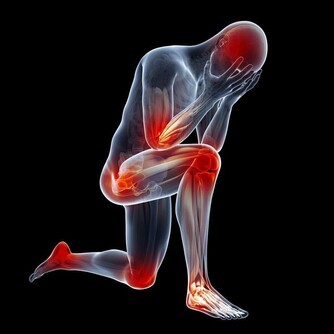

據媒體報導 ,銀監會非銀部主任李建華突發心梗辭世,年僅49歲,令人扼腕嘆息。 李建華的離世又是一齣悲劇,有人分析稱: 李主任表面看是心梗,而實際上是頸椎病所致。原因有兩點: 首先李主任本身頸椎就不好,當晚又加班至凌晨,而且一個姿勢很久導致頸部僵硬;

翻拍微信下同 其次當他入睡後依然維持了一個錯誤姿勢:側睡加頭低,導致頸部肌肉收緊,刺激了交感神經興奮,導致冠狀動脈平滑肌痙攣,心肌缺血,心梗而死。 頸椎病引起心臟病?是的! 專家說有可能!有一種心臟病就叫做頸源性心臟病,主要症狀包括如心前區作痛,心律失常,還會有胸悶不適感、心悸、氣促等。 看了下面數字,你怕不怕! 100個人中就有70個以上的頸椎病患者。 100個中風病症患者中有90%以上是由頸椎病引發的併發症。 100個腦癱病症患者中有63%以上是由頸椎病引發的併發症。 100個高位截癱病症者中有85%以上是由頸椎病引發的併發症。 100個猝倒死亡病症者中有95%以上是由頸椎病引發的併發症。 100個心肌梗塞病症者中有70%以上是由頸椎並引發的併發症。 100個腦血栓病症者中有80%以上是由頸椎並引發的併發症。 100個高血壓病症者中有60%以上是由頸椎並引發的併發症。 100個神經性胃潰瘍病症者中有75%以上是由頸椎並引發的併發症。 頸椎病有多要命?很危險! 更可怕的是,醫學上還發現頸椎病至少可引發全身70種病症,以下是幾種常見的病症。 1 吞咽不暢:吞咽時有梗阻感、食管內有異物感,少數人有噁心、嘔吐、聲音嘶啞、乾咳、胸悶等症狀。 2 視力障礙:視力下降、眼脹痛、怕光、流淚等,甚至還可能失明。 3 腹脹便秘:部分頸椎病患者因鄰近的頸交感神經受到刺激和損傷,使受其支配的內臟器官胃腸道蠕動減慢。 4 高血壓:血壓明顯升高,稱為「頸性高血壓」。由於頸椎病和高血壓皆為老年人的常見病,故二者常常並存。 5 胸痛:單側胸大肌和乳房疼痛,檢查時有胸大肌壓痛,這與頸六和頸七神經根受頸椎骨刺壓迫有關。 6 猝倒:站立或者走路時因突然扭頭出現身體失去支持力而猝倒,倒地後能很快清醒。 7 下肢癱瘓:早期表現為下肢麻木、疼痛、跛行,個別患者還有排便、排尿障礙,如尿頻、尿急或大小便失禁等。 8 老年痴呆:一旦頸椎間盤突出導致橫突孔變細、變形,會致使所供應的腦區發生供血不足,慢性腦缺血引起了遺忘等認知功能下降,長期以往最終會出現痴呆。 這頸椎病看著不起眼,可對我們的生命健康的威脅可是非常大! 奉勸頸椎不好的朋友千萬要當心,不要耽誤自己。在這裡提醒你,也希望你看到後提醒身邊的人:一定要關注自身的頸椎健康,別哪天被這頸椎病要了性命還不知道! 而很多人認為頸椎病不是很要緊的病,休息休息就好了,但是拖延下去,治療會越來越難,有的甚至要做手術治療,更嚴重的估計就會重演李建華的悲劇。所以勸大家及早預防,儘早治療! 脖子為什麼一轉就響? 因為我們身體的氣血供應不上,導致我們身體在變硬,關節在處於缺血狀態下的干磨。 氣血雙虧的身體相當於車軸里沒了油,很多人騎過自行車,知道如果車軸里缺油了,會感覺怎樣?一定是騎著費勁,一定會感覺裡面的滾珠轉動不靈活且有響動,有點類似我們的脖子響。只不過,自行車軸轉動靠的是油,而我們骨頭之間的轉動靠的是血液罷了。當我們血氣雙虧的時候,我們的骨關節之間的椎間盤,沒有充足的氣血供應,會形成干磨的情況,響動也就自然產生了。 骨關節為什麼會有病變? 1生理結構 人的頸椎和腰椎特別容易出問題,但胸椎卻好得多。這是因為我們的胸椎周圍有肋骨牽拉保護著,形成了一種力的相互作用,以確保我們的胸椎能夠保持中正。但是,頸椎和腰椎就不同了,它們沒有肋骨牽拉固定著,它們靠的是多組韌帶和小肌肉群。如果這些組織發生問題,就會導致我們的頸腰椎出問題。 2工作姿勢 當肌肉長期處於緊張狀態,就會感覺肌肉酸痛。正常情況下,如果胳膊腿酸了,我們活動一下,這樣的現象會很快消失,但是,用電腦就不一樣了,由於我們是長時間處於微弱的緊張狀態,這就好比溫水煮青蛙一樣,等我們查覺的時候,就已經晚了。它造成的後果就是,頸腰椎周圍的韌帶由於得不到充足的氣血供應,就會慢慢形成鈣化,兩側的牽拉受力開始不均勻,久而久之,椎間盤就會突出,擠壓周圍的組織和神經,頸腰椎病就會形成。 3工作環境 如果再加上工作環境的寒和濕比較嚴重,比如,在地下室工作、在空調底過的情況下工作,都會造成環境中的寒和濕進入到體內,特別是對於那些氣血本來就不夠通暢的肌肉和韌帶,會形成潛在的影響,加重了病變部位的病情。 4過食碳酸飲料 碳酸飲料會導致內脫鈣,久而久之,我們的骨頭變會得非常的疏鬆,那個時候,就不單純是骨頭響的問題了,而且還很容易導致骨折。 我們該如何調理? 下面介紹簡單易學的保護頸椎,甚至可以治好頸椎病的方法,大家一定要記好了! 1多多活動 天天以電腦為伴的朋友,用一會兒電腦,就要起來活動一下,同時活動一下脖子,但千萬不要做360度的圓周運動,只作90度向左轉,向90度的向右轉的動作,以確保我們脖子兩側的韌帶在短時間內,都能夠得到均衡的牽拉,以改善局部供血。而且切記動作要緩慢。 2不要讓頸部受涼 其是不要讓頸椎吹到冷風。頸椎受涼之後寒濕之氣很容易進入體內,而加重頸部韌帶的鈣化。 3杜絕碳酸飲料 減少包括可樂在內的一切碳酸飲料的攝入,因為這種溫水煮青蛙的過程是漸進的,因此很難被人們重視。 4打通經絡 這點最為重要。如果是脖子不舒服,最簡單的方法就是以自己的下巴寫米字,一天做一次即可,或在桌子邊擱後溪穴,以確保頸椎部的血液循環,使自己的頸椎摸著是溫暖的,而不是冰涼的。 5滾一滾、滾出好脊椎 站立歪斜或坐姿不端正、習慣性翹腳、長時間玩手機或者是坐在電腦前都會造成我們脊椎歪曲不直,脊椎一旦彎曲歪斜,很多毛病會跟著來。 中老年朋友可以常常做滾背的動作,矯正脊椎,甚至有人長了骨刺也可以治癒哦!每天勤快108下(來回一次算一下),骨刺免開刀,不用快慢慢做,矯正脊椎自己來! 滾背方式: 1、並腿屈膝坐在地上,兩手環抱住小腿,自然呼吸別太急促,收腹拱背,身體往後從尾椎、腰椎一節一節觸及地面,剛開始腳還先不用越過頭,多做幾下後再視自己身體狀況,然後滾到胸椎、頸椎,腳尖朝上,漸漸地雙腳越過頭,腳打直腳尖著地。